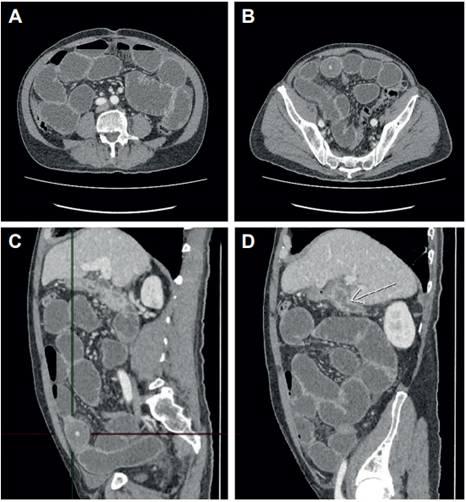

Figura 1. Imágenes de la tomografía computarizada de abdomen y pelvis. A. Dilatación difusa de asas intestinales delgadas de hasta 4,8 cm, sin signos de sufrimiento de asa ni neumoperitoneo. B. Zona de transición en el tercio distal del íleon; se aprecia imagen redondeada que corresponde al cálculo que ocluye la luz intestinal. C. Proyección lateral donde las líneas señalan la ubicación del cálculo que ocluye el íleon. D. Vesícula biliar escasamente distendida, con engrosamiento difuso y realce de sus paredes, con burbujas gaseosas en su interior; la flecha blanca muestra una comunicación de la vesícula con la segunda porción del duodeno y un aparente trayecto fistuloso hacia el margen anterior con colección subfrénica laminar. Asociado se observa aumento en la densidad y estriación de la grasa pericolecística.

Se presenta un pacientae de 65 años, con cuadro clínico de varios meses de dolor abdominal cólico intermitente, asociado a perdida no intencionada de peso. Consultó a otra institución por una semana de dolor y distensión abdominal, con múltiples episodios eméticos, donde consideraron que cursaba con obstrucción intestinal e iniciaron manejo medico con sonda nasogástrica. Ante la falta de respuesta después de cuatro días, lo remitieron a nuestra clínica y se realizó tomografía computarizada (Figura 1) donde se observó obstrucción intestinal mecánica del intestino delgado, con zona de transición en el íleon distal, causada por estructura redondeada que ocluye la luz intestinal, sin signos de sufrimiento de asas. Adicionalmente referían signos de colecistitis crónica, con trayecto fistuloso de la vesícula biliar a la segunda porción del duodeno y otro trayecto fistuloso que se comunicaba con colección laminar subdiafragmática, por lo que se hizo diagnóstico de íleo biliar y se decidió llevar el paciente a cirugía.